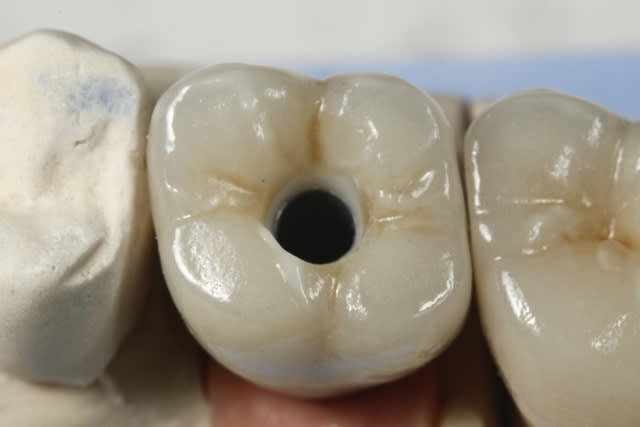

Exemple ici d'un cas ant avec

- une facette

- une ccm sur moignon metal implantaire

- une ccm sur inlay core

- une ccm a tenon.